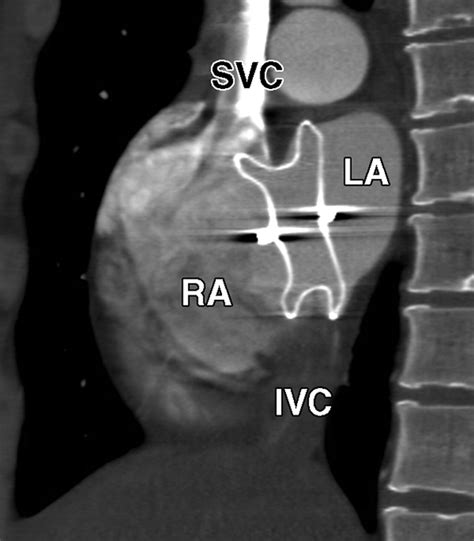

The Amplatzer Septal Occluder is specifically designed to address this by sealing the defect. It is essentially a self-expanding, double-disk device made from a flexible nitinol wire mesh. Once placed, it creates a "sandwich" effect that covers both sides of the hole, allowing the patient's own tissue to grow over the device over time, effectively healing the septal wall.

• Deployment: The Amplatzer Septal Occluder is pushed through the catheter. The left atrial disk is deployed first to anchor the device, followed by the right atrial disk.